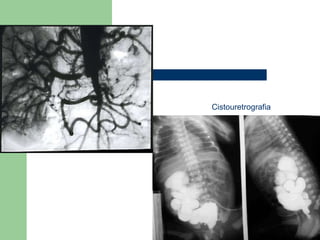

ESTUDIOS POR IMAGEN Solo si se sospecha de infección renal o alteración anatómica. Rx de riñón, uréteres y vejiga, cistouretrografía miccional, ecografía renal, UVI, TAC y Gammagrafía. Exploraciones especiales: cistoscopia y en ocasiones pielografía retrograda para descartar uropatía obstructiva.

Cistouretrografia

ESTUDIOS POR IMAGENSolo si se sospecha de infección renal o alteración anatómica. Rx de riñón, uréteres y vejiga, cistouretrografía miccional, ecografía renal, UVI, TAC y Gammagrafía. Exploraciones especiales: cistoscopia y en ocasiones pielografía retrograda para descartar uropatía obstructiva.